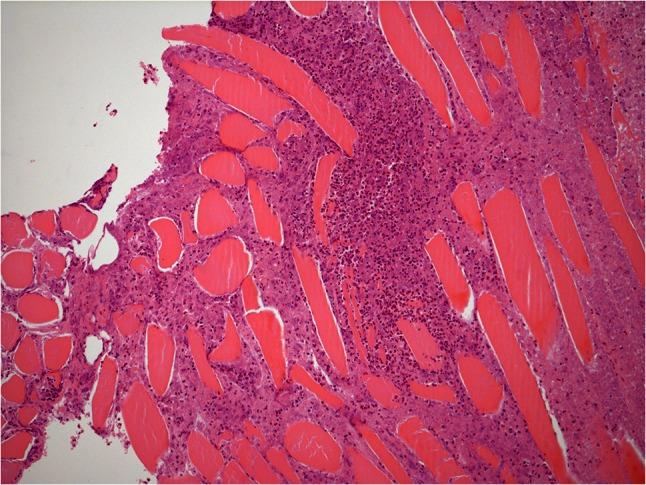

使用LARS韧带重建跟腱后出现的伴有肉芽肿的异物反应。

Foreign body reaction with granuloma following Achilles tendon reconstruction with the LARS ligament.

Ligament reconstruction with the LARS ligament has been a popular choice owing to its low-complication rates compared with previously commercially available grafts. The non-active nature of the implant also meant that there were no foreign body reactions that had been described with other synthetic grafts. We describe the first reported case of a granulomatous foreign body reaction in a LARS ligament Achilles tendon graft and a technique to reconstruct the tendon following its excision.

与先前市售的移植物相比,使用LARS韧带进行韧带重建因其低并发症发生率而成为一种流行的选择。该植入物的非活性性质还意味着不存在其他合成移植物所描述的异物反应。我们报道了首例LARS韧带跟腱移植物发生肉芽肿性异物反应的病例,以及一种在切除该移植物后重建肌腱的技术。